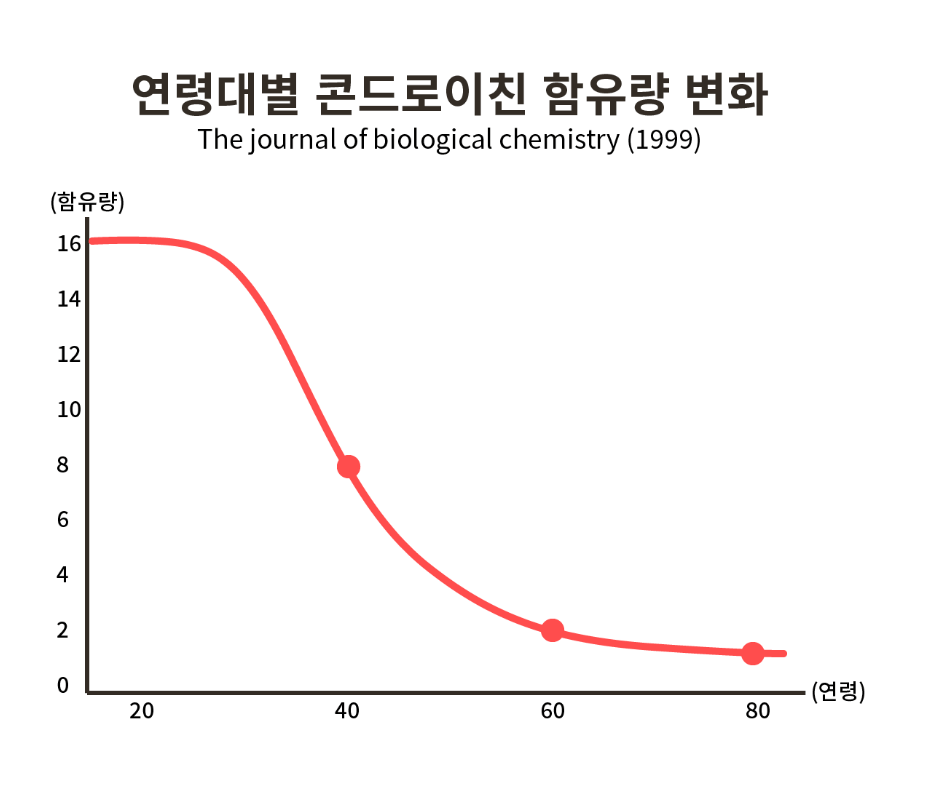

- 관절엔 콴첼 콴첼 콘드로이친 제품 효능과 직결된 콘드로이친(Chondloitin)은 연골과 관절의 구성하는 주요 성분이지만 불행히도, 나이가 증가할수록 농도가 점차 감소하게 됩니다.

- 실제로, 아래의 '연령대별 콘드로이친 함유량 변화' 그래프를 통해 알 수 있듯이, 연구에 따르면 40대가 되면 연골 속 콘드로이친은 20대 비해 절반 이하로 감소하며, 60대 무렵에는 거의 소멸된다고 밝혀진 바 있습니다.

- 하지만, 외부로부터 체내 복용 시 연골 감소 억제에 도움을 주는 것이 입증되었습니다.

- 실제로, 콘드로이친 섭취 후 각각 6개월, 12개월 간격을 둬 살펴본 연구에서는 대조군에 비해 섭취군에서 연골이 적게 감소하며,

- 연골의 부피 손실률이 큰 폭으로 감소된 점을 확인하였다는 점 주목할 필요 있습니다.